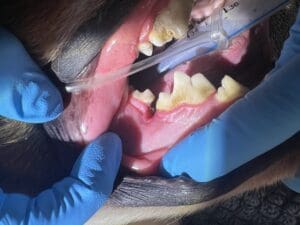

When a dog aggressively chews on a stick, small pieces of wood can break off and get stuck between the teeth. Usually this happens near the back of the mouth, as the premolars and molars are the main teeth used for chewing. Unlike a person, a dog isn’t going to reach for a toothpick, and it is easy for this to go unnoticed. Over time, the presence of this material (called a foreign body), causes inflammation and infection which can lead to periodontal disease and severe bone loss. In severe cases, this can become so advanced that nothing can be done but extract the affected teeth.

Picture showing a defect in a dog’s right mandible between the first and second molar, caused by stick impaction.